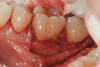

Fig 1. Tooth No. 19 at presentation, buccal view.

Fig 2. Tooth No. 19 at presentation, occlusal view. Note the thickness of the soft tissue and width of keratinized tissue.

Fig 3. Distal probing depth of 10 mm at tooth No. 19.

In the case presented, a 56-year-old healthy nonsmoking male patient, diagnosed with periodontitis stage III, localized, grade B, had been under care in a private practice periodontal office (RAL) for 25 years. He had a history of good compliance with his treatment (full-mouth plaque score <20%). During the COVID-19 pandemic, the patient missed three supportive periodontal therapy (SPT) visits over a year, resulting in periodontal breakdown interproximal between teeth Nos. 18 and 19 (mandibular left second and first molars, respectively). At his most recent periodontal maintenance visit, significantly increased periodontal probing depths of up to 10 mm with bleeding on probing were noted (Figure 1 through Figure 3). The periapical radiograph revealed a deep, narrow three-wall intrabony defect at the distal aspect of tooth No. 19, with class I buccal furcation involvement (Figure 4). According to the periodontal risk score (PRS),15 formerly known as the Miller-McEntire periodontal prognosis index, the tooth prognosis at the patient's initial examination was "good" (score = 5), taking into account that he was unaware of his hemoglobin A1C (HbA1c) levels. This scoring motivated the patient to be tested, and his follow-up HbA1c was <6%, thus reducing his PRS to 3, which was considered "excellent," as the PRS target goal for regenerative procedures is a score of <5.15